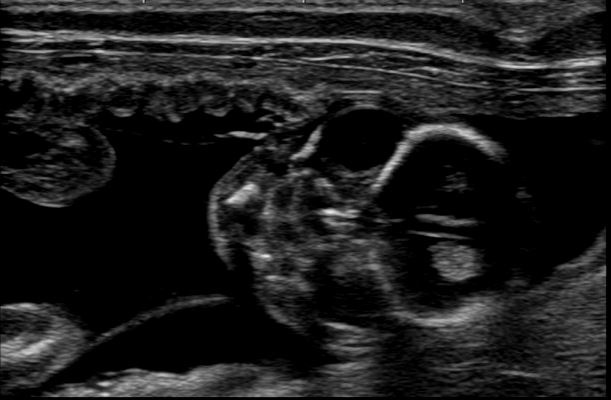

子宮内胎児死亡

1頭目は心臓の動きが確認できるが、2頭目は確認できず羊水に膿らしきものがみられる。他の胎児(胎嚢)は、数日前まで確認できた胎児が存在せず、死亡・吸収された状態。妊娠期のおりものには注意が必要。